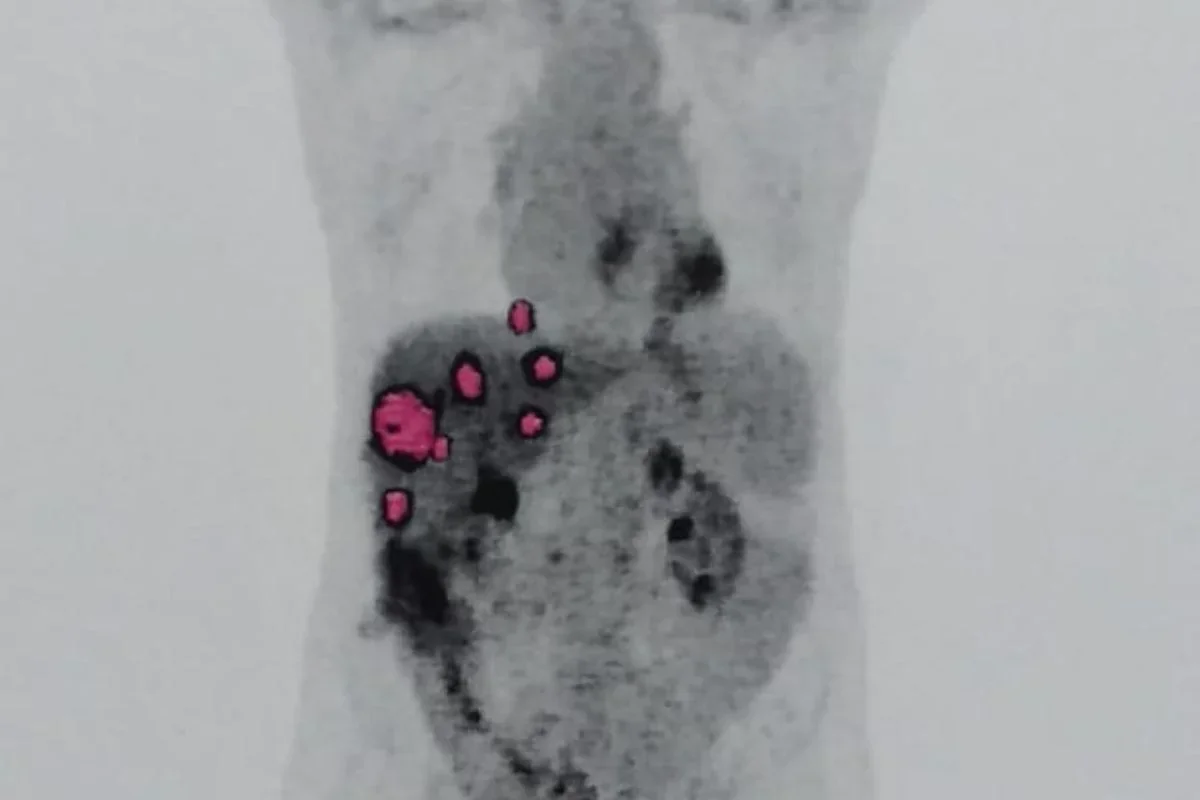

Em maio de 2024, Geraldo passou por um novo transplante. Contudo, em agosto, exames detectaram que o câncer havia se espalhado para os pulmões. Especialistas afirmam que a doadora provavelmente já tinha o câncer, que não foi identificado antes da doação. Casos como esse são raríssimos, com incidência inferior a 0,03%.

Com metástase sem cura, Geraldo enfrenta sessões contínuas de quimioterapia e não pode mais trabalhar. A família pede esclarecimentos e mudanças urgentes nos protocolos de transplante para evitar novos casos semelhantes.